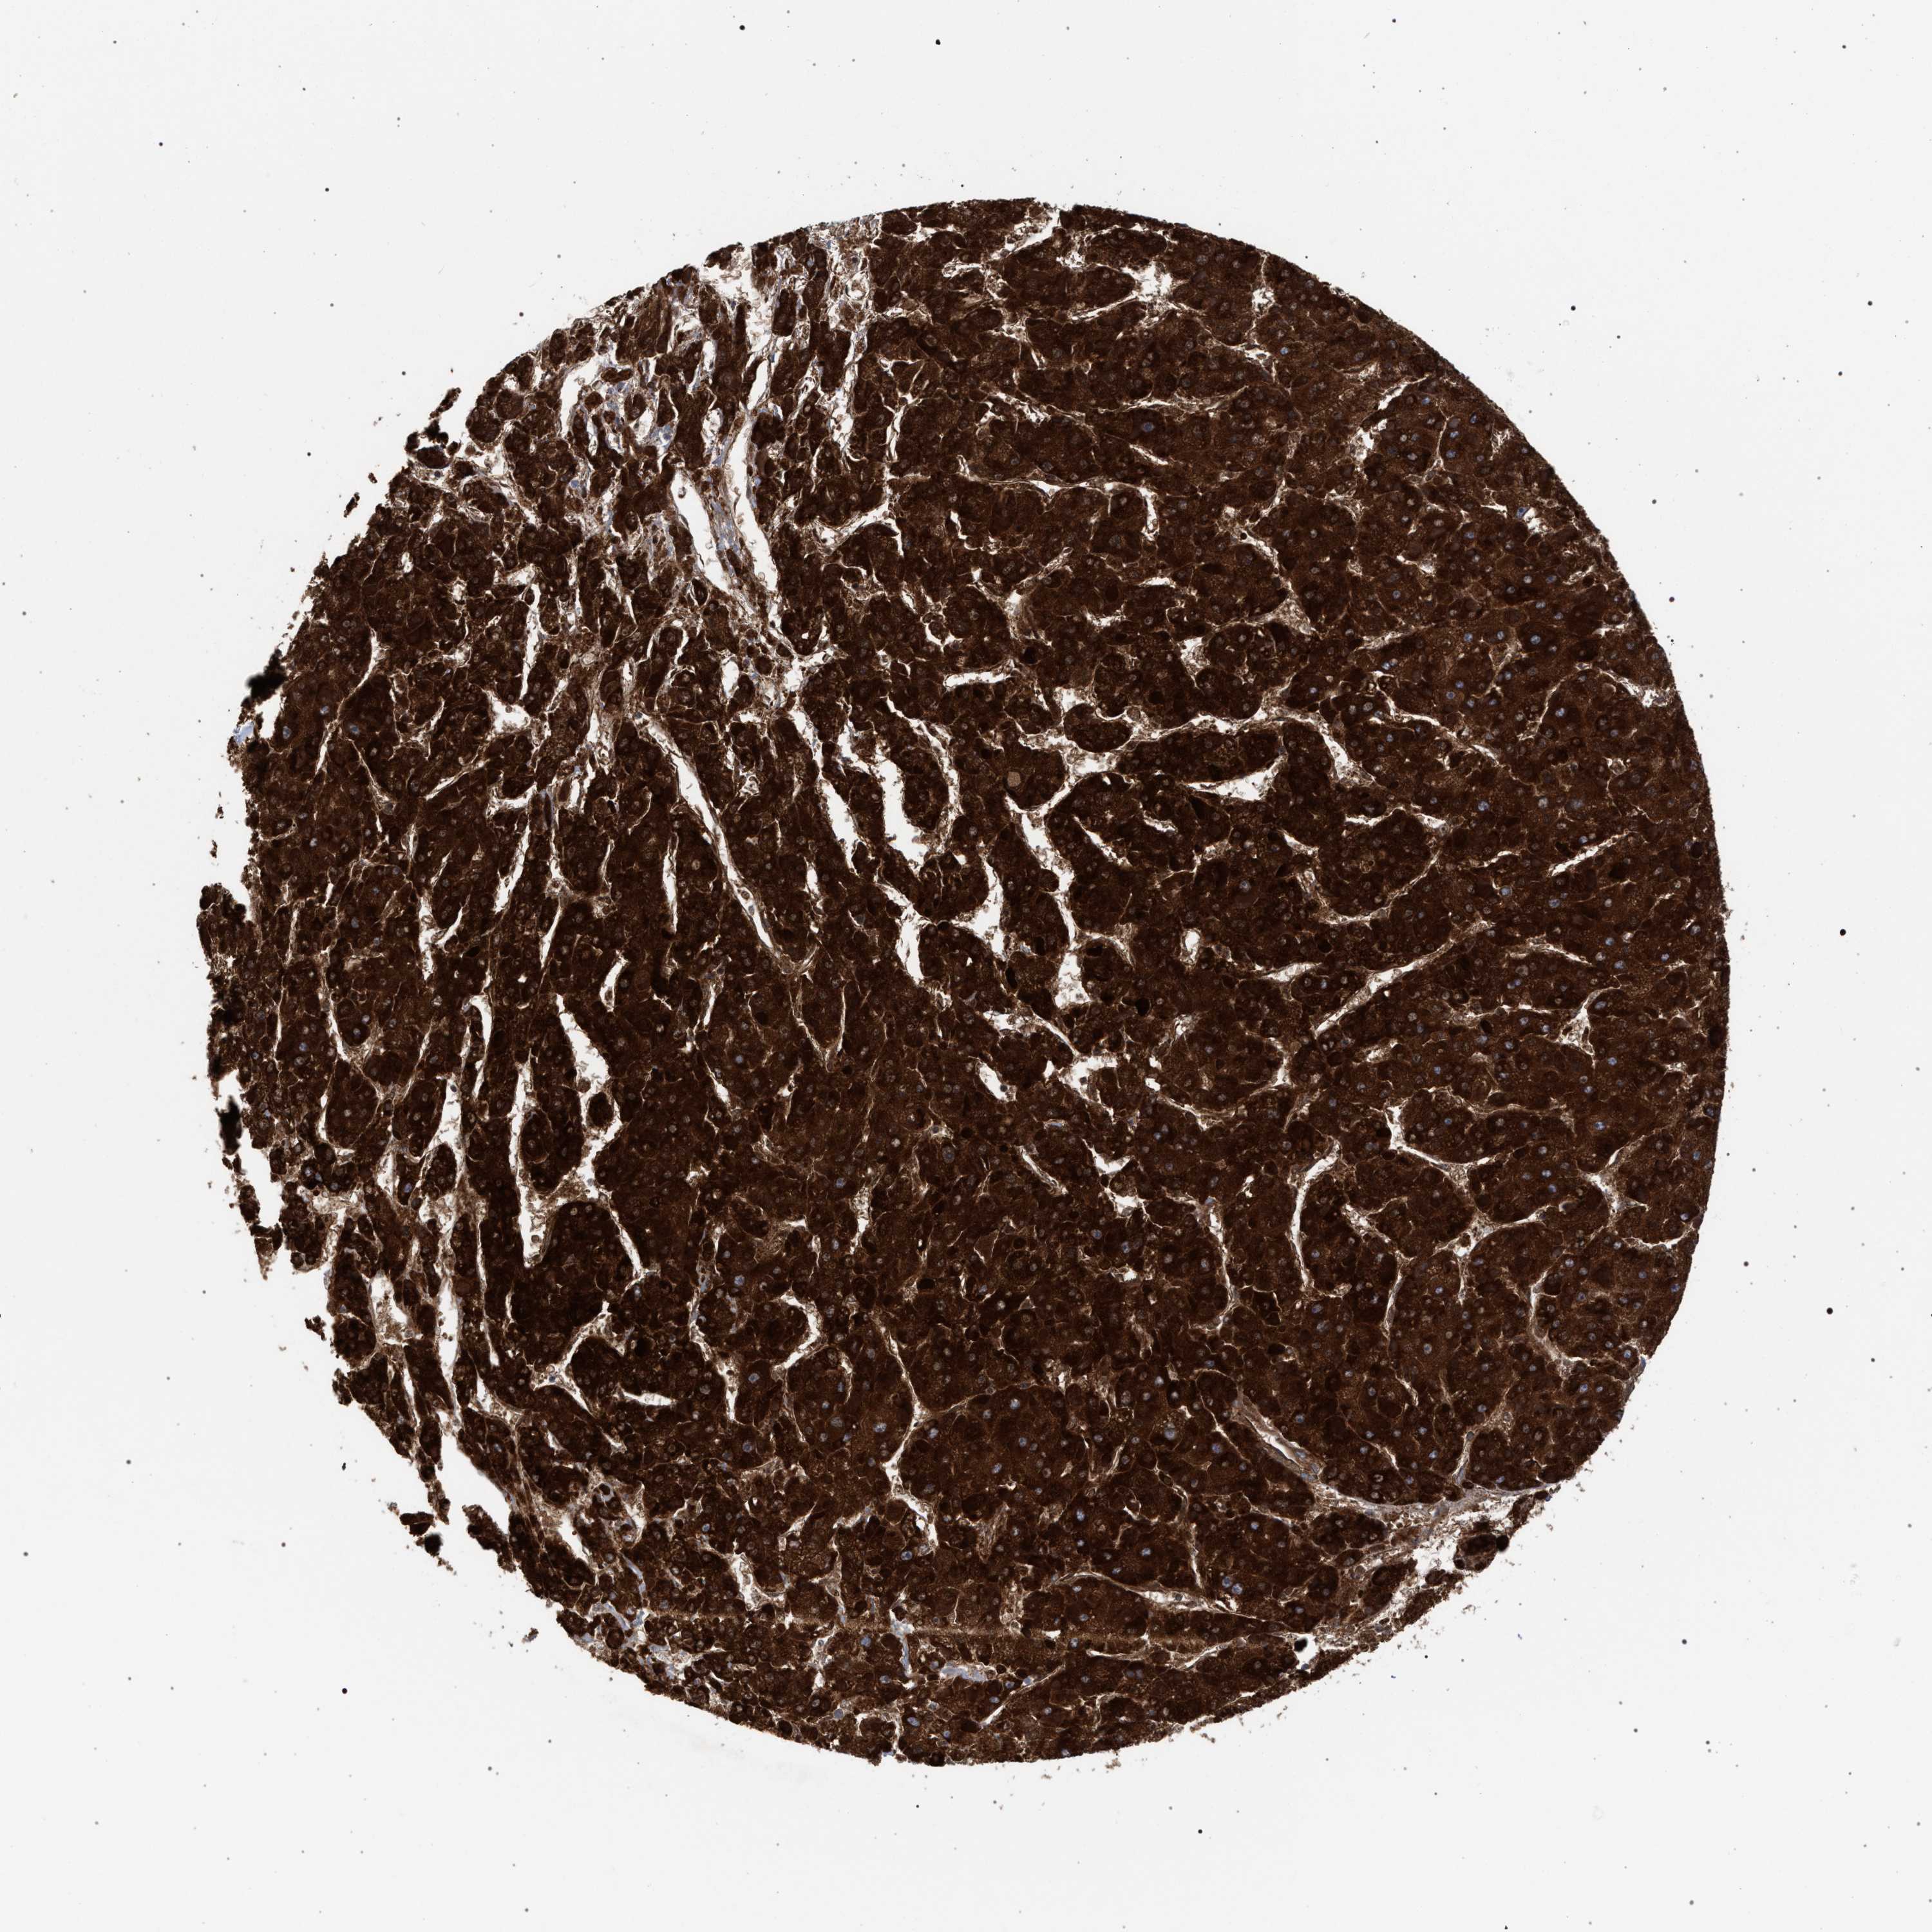

LIVER CANCER - Protein expressioni

A mouse-over function shows sample information and annotation data. Click on an image to view it in a full screen mode. Samples can be filtered based on level of antibody staining by selecting one or several of the following categories: high, medium, low and not detected. The assay and annotation is described here.

Note that samples used for immunohistochemistry by the Human Protein Atlas do not correspond to samples in the TCGA dataset.

Antibody stainingi

Antibody staining in the annotated cell types in the current human tissue is reported as not detected, low, medium, or high, based on conventional immunohistochemistry profiling in selected tissues. This score is based on the combination of the staining intensity and fraction of stained cells.

Each image is clickable and will lead to virtual microscopy that enables deeper exploration of all samples and also displays staining intensity scores, fraction scores and subcellular localization as well as patient and tissue information for each sample.

Antibody HPA022130

Antibody HPA031626

Staining

High

Medium

Low

Not detected

Intensity

Strong

Moderate

Weak

Negative

Quantity

>75%

75%-25%

<25%

None

Location

Nuclear

Cytoplasmic/membranous

Cytoplasmic/membranous,nuclear

Cholangiocarcinoma

Carcinoma, Hepatocellular, NOS